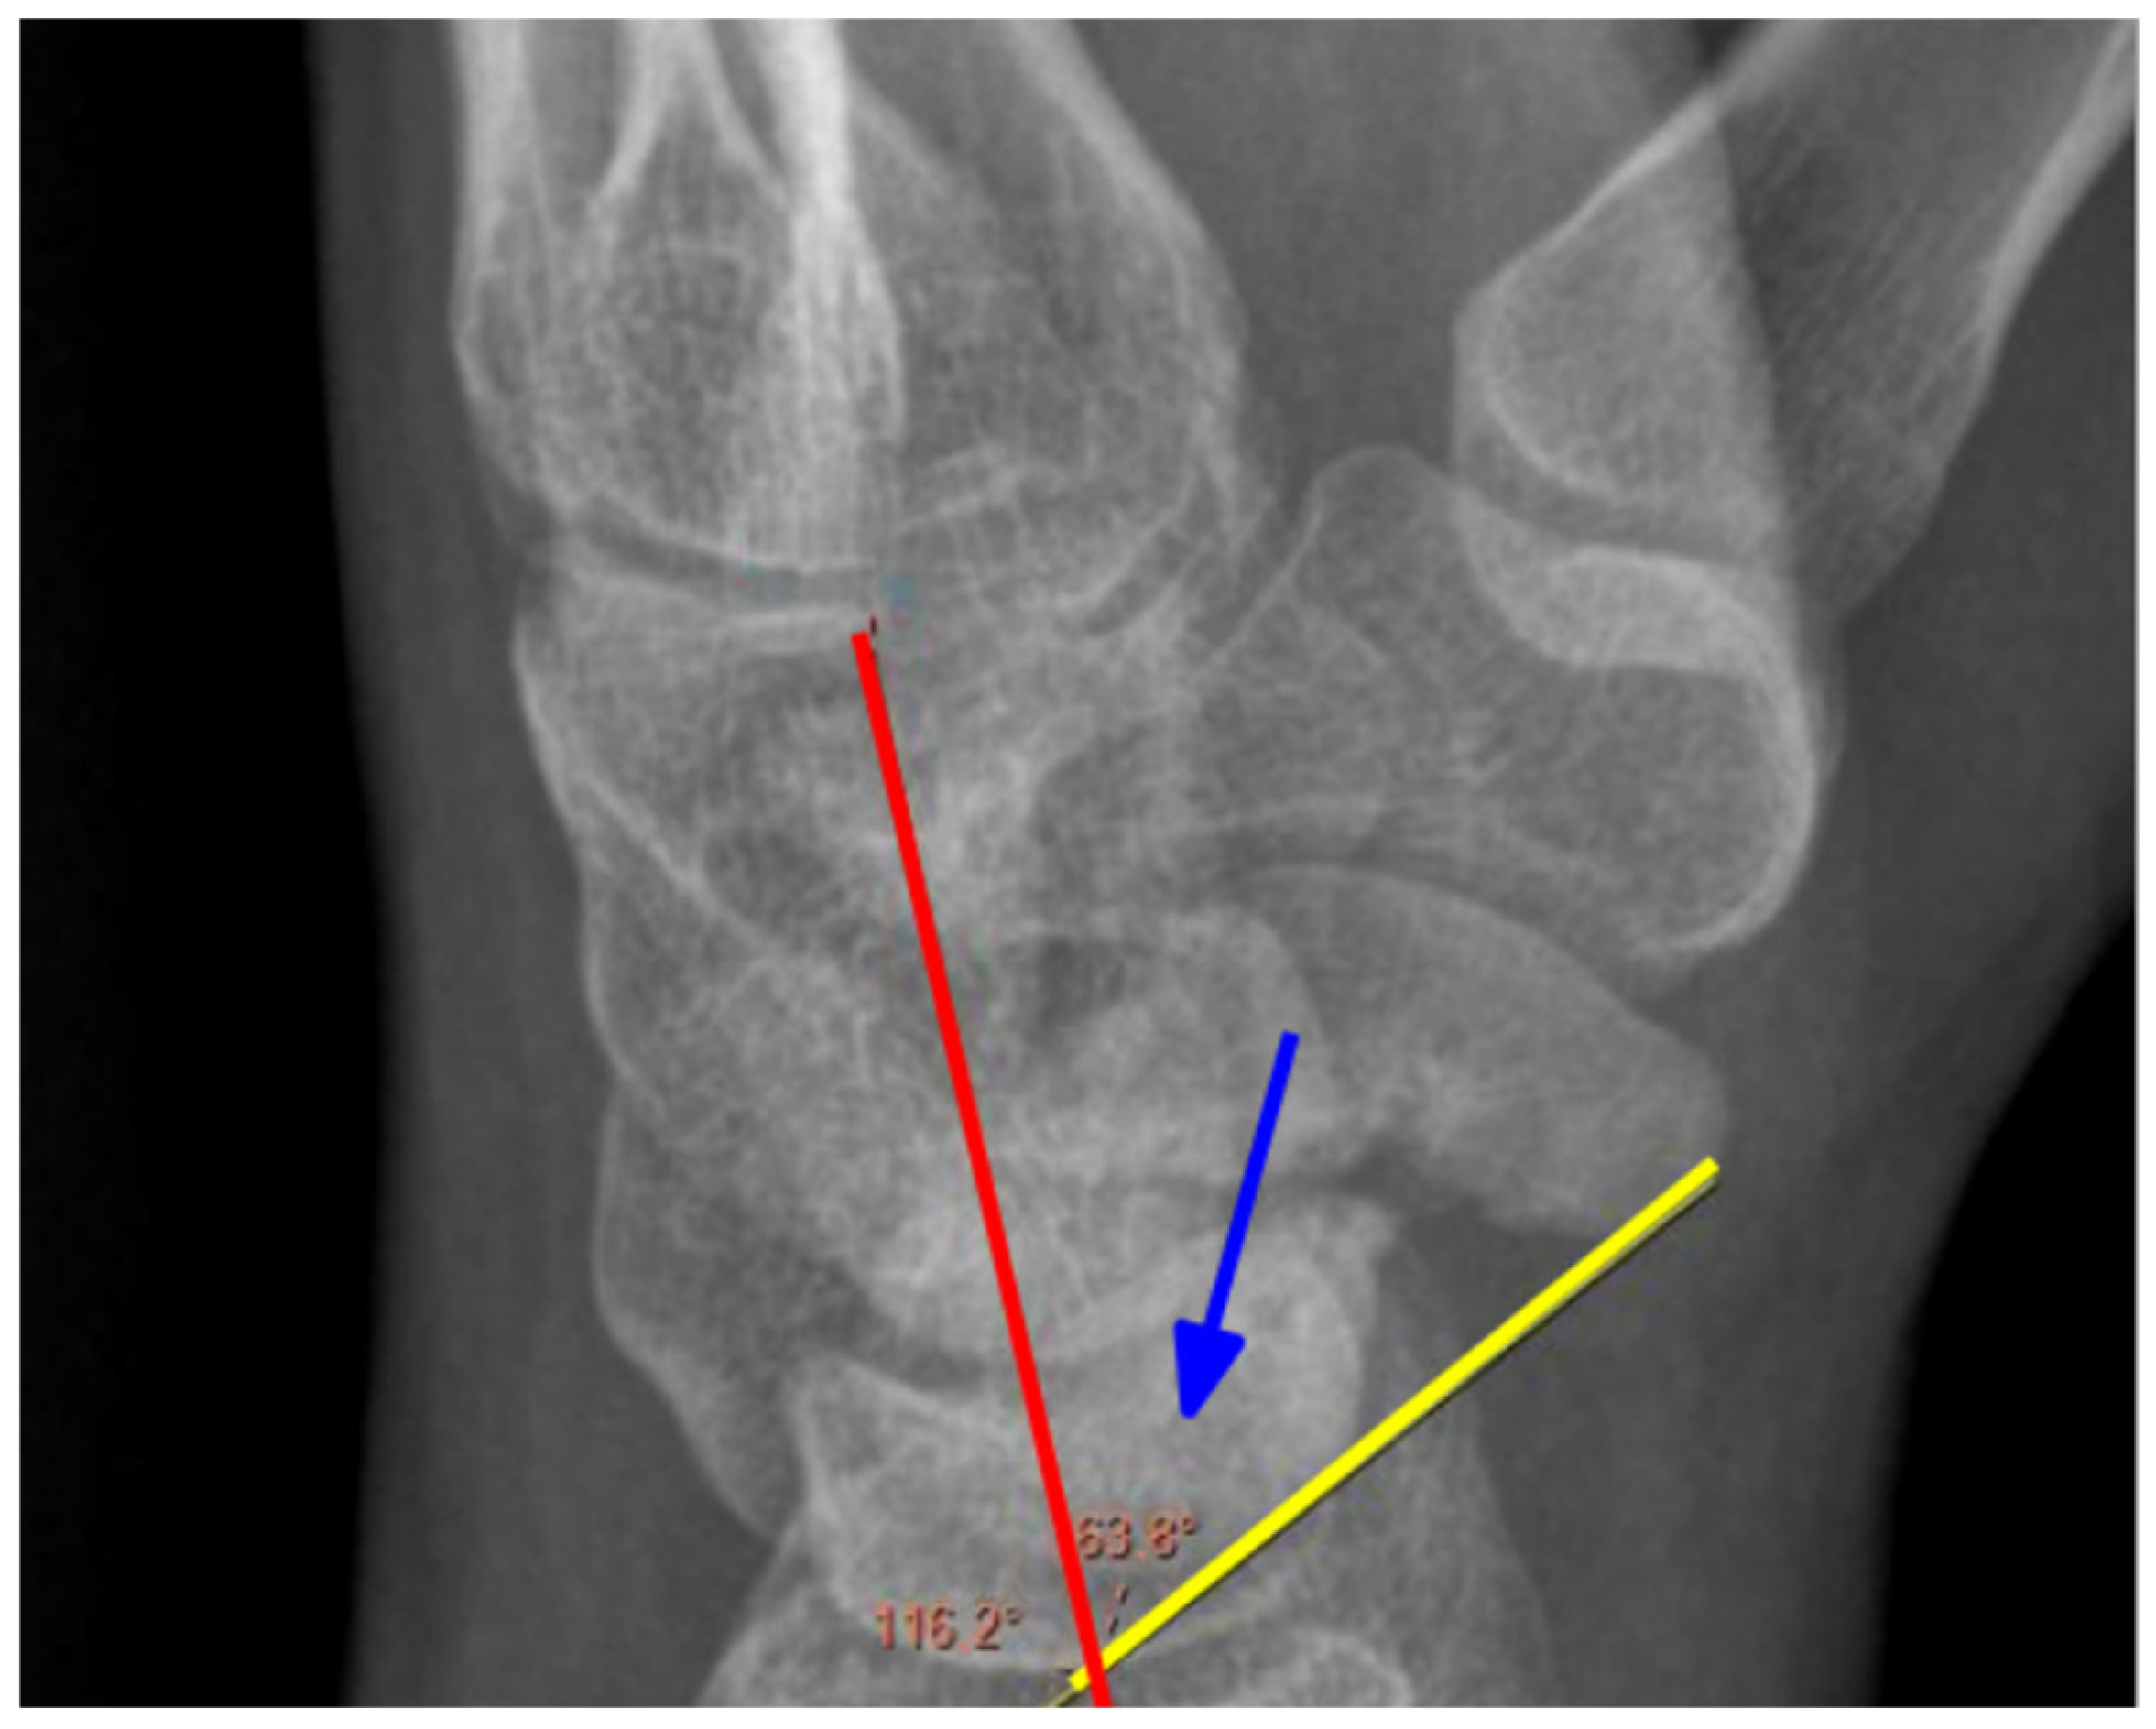

2.2. Radiological Assessment

| CLA | Capitolunate angle |

| SLA | Scapholunate angle |

| SCA | Scaphocapitate angle |